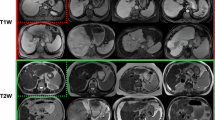

To interpret the learning outcomes of MAOSS, we employ an attribution technique called Integrated Gradients (IG)40. This machine learning-based method is designed to visualize the influence of different input components on the model’s output using heatmaps, where larger values indicate a higher degree of influence. By attributing the output MAOSS score to the input 3D-liver image, IG allows us to visualize the specific alterations caused by steatosis in the liver at the voxel level. Additionally, it demonstrates that our MAOSS model has effectively learned the features associated with steatosis. Given that CT attenuation is a critical feature associated with steatotic changes, we examined the distribution of liver attenuation and integrated gradients. Figure 4a present the density plots for liver attenuation (Hounsfield units) and IG values across different steatosis grades (S0-S3), demonstrating a clear stratification among these grades. Notably, the IG values exhibit distinctive distributions across different steatosis grades, with severe steatosis (S3) showing a distinct peak and narrower spread compared to other grades. This indicates that the IG method effectively captures variations in voxel intensities associated with different degrees of hepatic steatosis. The scatter plot illustrates the joint distribution of liver attenuation and IG, which demonstrates an exponential correlation of IG values and liver attenuation values. Figure 4b provides an intuitive spatial mapping of IG on 3D liver images for representative cases across various steatosis grades, validated against corresponding MRI-PDFF measurements. As depicted, with increasing fat infiltration, the IG exhibit increasingly heterogeneous patterns, with elevated values localized in regions of pronounced fat accumulation. The spatial distribution of fat accumulation closely aligns with the MRI-PDFF reference, not only in uniformly distributed steatosis cases (Fig. 4b) but also in non-uniform steatosis cases (Fig. 4c). This observation suggests that MAOSS is capable not only of distinguishing between steatosis grades but also of effectively identifying regions of interest where steatotic alterations occur within the liver.

a Density plots show histologically-derived testset (internal and external) distribution of mean liver attenuation (in Hounsfield units), mean liver integrated gradients (IG), liver attenuation against integrated gradients for whole liver, showing MAOSS learned an exponential association between IG and liver attenuation with distinctive joint distribution. b The 3D saliency mapping of IGs overlaid on the cropped liver region in NCCTs from different viewpoints demonstrates that IGs spatial distribution in correlation with steatotic alternation on MRI-PDFF. Patient A: 66 year-old male with overall liver MR-PDFF 2% without steatosis. Patient B: 57 year-old female with MR-PDFF 14% (mild-moderate steatosis). Patient C: 53 year-old female with MR-PDFF 37% (severe steatosis). c The saliency map of MAOSS matches findings of steatotic (red arrows) and non-steatotic areas (white arrows) on MRI-PDFF maps in the non-uniformly distributed steatosis cases. None (S0), mild (S1), moderate (S2), and severe (S3) steatosis.